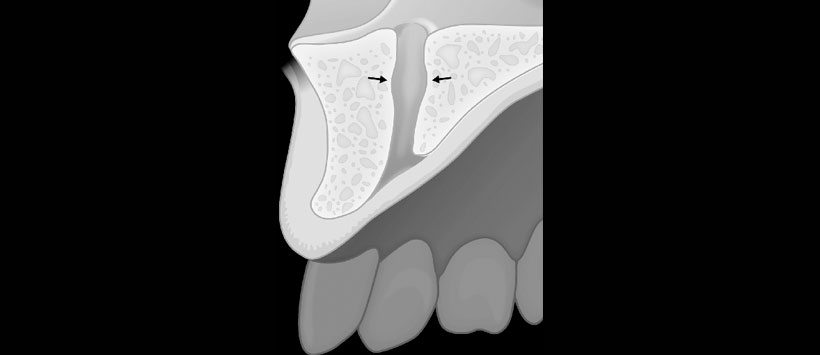

Las dimensiones del CNP, incluyendo la longitud, el ancho a la mitad y el diámetro del foramen incisal y nasal, se midieron en planos sagitales y axiales de CBCT. Además, se realizó una evaluación de los signos de abultamiento, la osteólisis apical del incisivo y su fusión con el CNP.

- Figura 1: Vista esquemática de las diferentes medidas realizadas en los planos sagitales de las imágenes CBCT (nº 1 a nº 4).